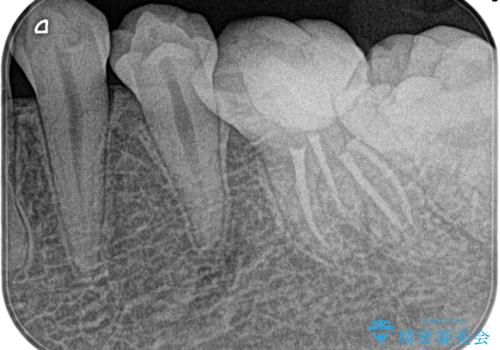

- 1週間前から左下奥がズキズキして、冷たいもので激痛を主訴に来院されました。

不可逆性歯髄炎の診断のもと根管治療を行なっております。